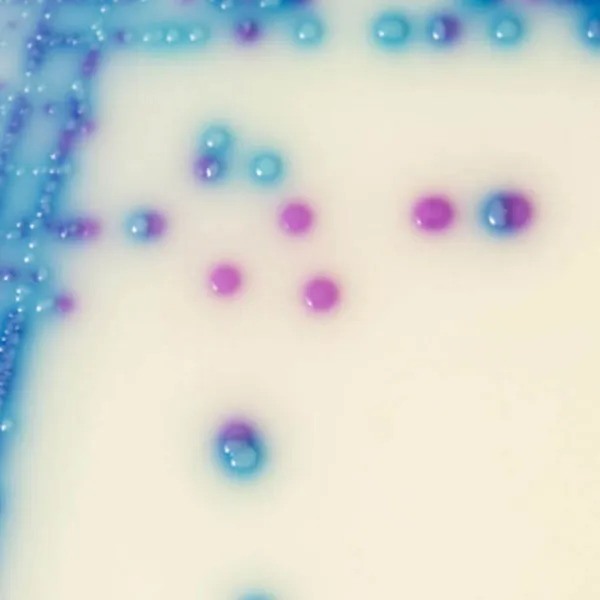

Hình thái khuẩn lạc

ERV. faecalis/ERV. faecium

Hồng đến tím nhạt

E. gallinarum/E. casseliflavus

Màu xanh hoặc bị ức chế

2. Màu sắc khuẩn lạc đậm: Trong CHROMagar™ VRE, các chủng VRE faecalis và VREfaecium có thể dễ dàng phân biệt thông qua màu sắc khuẩn lạc. Ngược lại, trong môi trường thạch cổ điển để phát hiện VRE (Bile Esculine Agar bổ sung vancomycin):